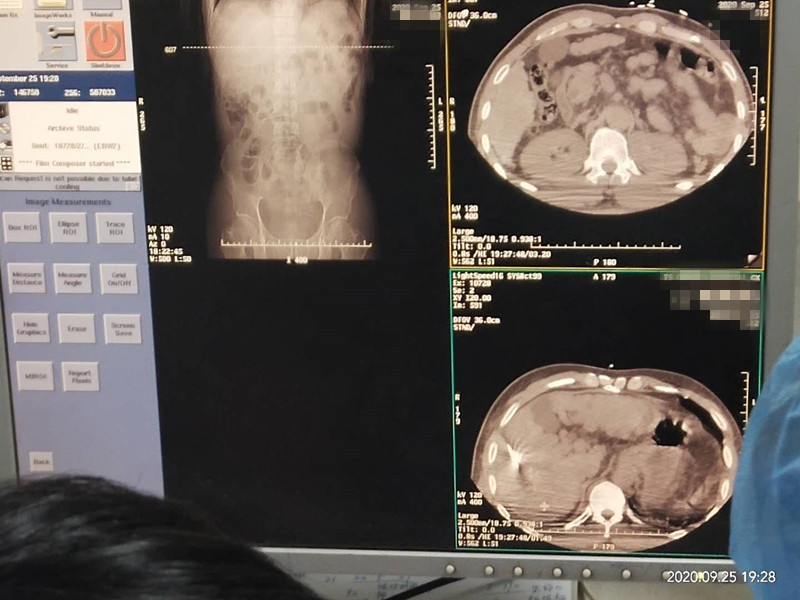

53岁患者肝部氩氦刀冷冻消融